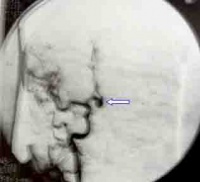

对患者进行TCD监控和头颅CT复查,发现有脑血管痉挛或脑积水及时处理,怀疑动脉瘤或血管畸形,通过DSA确诊,神经外科进行处理。脑血管造影是确诊动脉瘤的金标准,一般选在发病后三天内或三周后。

通过病史、神经系统检查、脑血管造影及头颅CT检查,可协助病因诊断与鉴别诊断。除和其它脑血管病鉴别外,还应与下列疾病鉴别:①脑膜炎:有全身中毒症状,发病有一定过程,脑脊液呈炎性改变。②脑静脉窦血栓形成:多在产后发病或病前有感染史,面部及头皮可见静脉扩张,脑膜刺激征阴性,脑脊液一般无血性改变。